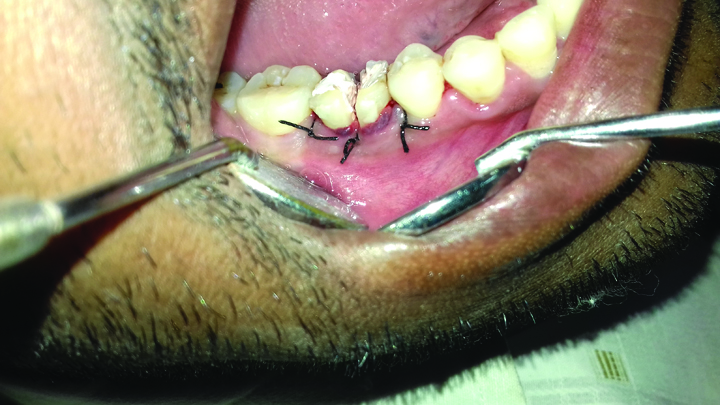

After two weeks, the post obturation restoration was done with composite resin (TPH, Dentsply) and then a surgical procedure was carried out for intentional bicuspidisation of the tooth. After removal of the orthodontic band, a full thickness Kirkland flap was raised with the cervicular incision extending from the distal surface of the mandibular second premolar to the midfacial surface of the mandibular second molar [Table/Fig-6]. After flap elevation, the tooth was dissected with the help of a long shank tapered fissure carbide bur to make vertical cuts towards the bifurcation area. All faces of the mesial and distal roots were rounded up and the spurs were smoothened. After irrigation with saline solution, the flap was repositioned and sutured with 3/0 silk sutures [Table/Fig-7].

Bicuspidisation carried out and flap sutured with 46.